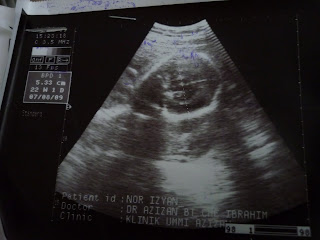

damia dlm perut mama

ni gambo scan mia lam perut mama.. mase ni dah 7bln.. mama saje snap gambo ni..bowingg tunggu abah wak kije..